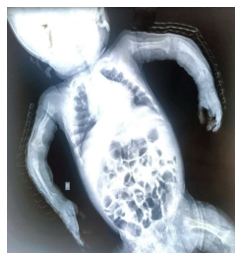

A very preterm neonate (28+5 weeks GA), extremely low birth weight of 730 g (Small for gestational age), born by preterm vaginal delivery with a significant antenatal history of preeclampsia in the mother and absent end diastolic flow on antenatal Doppler developed perinatal depression requiring bag and mask ventilation for one minute. The baby had respiratory distress syndrome and was on oxygen support for three days. Intravenous fluid was tapered and stopped by day 2, and Ryle's tube feeds were introduced gradually. Routine preterm screenings were done, which showed grade 2 intraventricular hemorrhage on the ultrasonography skull on day of life 3 (DOL-3), which was resolved on subsequent scans. Zone 2 stage 3 retinopathy of prematurity was noted on ophthalmic evaluation and metabolic bone disease workup was positive on DOL-28 with a vitamin D value of 4.3 ng/ml, calcium was 8.0 mg/dl, and phosphorus was 3 mg/dl, for which supplements were increased to therapeutic doses. The baby was gradually shifted to oral bondla feeds and had adequate weight gain. On DOL-80, painful, restricted motion of the left upper limb and right lower limb was noticed, for which an infantogram was done. The infantogram showed marked osteopenia and multiple fractures detected in the upper limb: right humerus mid-shaft, right proximal ulna, left distal end radius and right tibia fracture (Figures 1 and 2). Repeat vitamin D and calcium levels were done, which were in the normal range (Table 1). In view of multiple fractures and dysmorphism (proptosis, low-set ears, triangular facies, pointed chin), a clinical exome was sent suspecting skeletal dysplasia. The exome detected LRP5 mutation s/o OPPG. A detailed ophthalmic evaluation was done to screen for vision, and retinal pathologies, but the ophthalmic examination was normal. Supplements were continued and fractures were treated conservatively with casts. On follow-up, the baby was doing well and had good weight gain. Although fractures were healed, there was a mild left arm deformity post-healing (Figure 3). The plan is to start bisphosphonates, and conduct close IQ, developmental, and ophthalmic assessments for early detection and intervention.

Figure 1. Osteopenia and multiple fractures detected in the upper limb: right humerus mid-shaft, right proximal ulna, left distal end radius

Figure 2. Fracture at right tibia